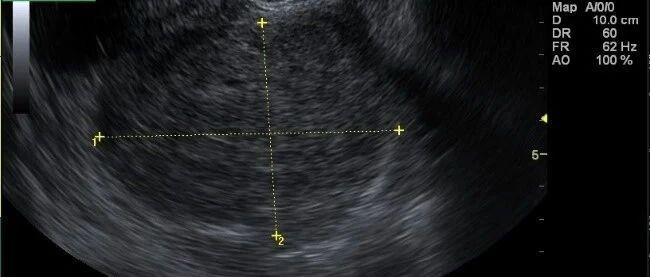

急诊床旁彩超诊断腹主动脉瘤破裂 2 例 丁香园超声时间 · 公众号 · 医学 · 1 年前 · |